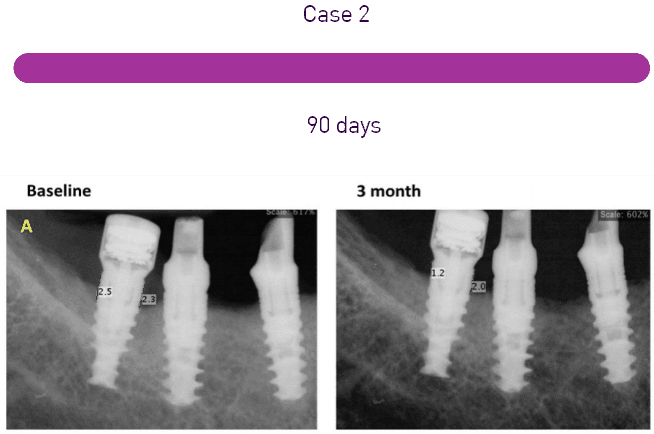

The systematic review by Risolo et al. sheds light on the effectiveness of reconstructive surgical techniques in treating peri-implant osseous defects compared to conventional peri-implant flap surgery. The study analyzed data from nine published articles involving 442 patients. It was found that reconstructive techniques showed a greater extent of defect fill compared to conventional surgical methods. However, when it comes to clinical measures of peri-implant disease, such as bleeding on probing and reduction of probing depth, no significant differences were observed between open flap debridement and regenerative surgery over a 12-month period.